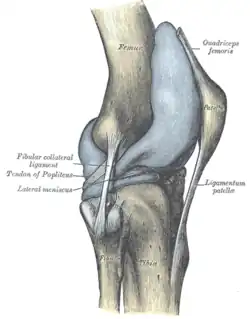

Das Knie hat zwei Seitenbänder: ein inneres (Ligamentum collaterale tibiale) und ein äußeres (Ligamentum collaterale fibulare). In Streckstellung sind beide Seitenbänder (auch Kollateralbänder genannt) gespannt und verhindern somit die Drehbewegung, in Beugestellung verkleinert sich der Krümmungsradius, Ursprung und Ansatz nähern sich einander an und die Bänder sind infolgedessen entspannt. Beide Seitenbänder stabilisieren das Kniegelenk in seitlicher Richtung (Frontalebene), damit ein Wegknicken in eine O-Bein-Stellung (Genu varum) oder X-Bein-Stellung (Genu valgum) verhindert wird.

Das Außenband (Ligamentum collaterale fibulare bzw. laterale) ist ein kräftiges Band, das in seinem dorsalen Abschnitt zylinderförmig vom Aufsatz des seitlichen Oberschenkelknochens (Epicondylus lateralis femoris) zum Wadenbeinkopf (Caput fibulae) zieht. Es hat keine feste Verbindung zur Gelenkkapsel und den Menisken.

Das 2013 beschriebene anterolaterale Ligament zieht vom gleichen Ursprung wie das Außenband zum anterolateralen Schienbein und ist dort mittig zwischen Wadenbeinköpfchen und Tuberositas tibiae verwachsen. Zudem ist es fest mit dem Außenmeniskus verbunden.[14]

Hintere Bandsicherung

Auf der hinteren Seite des Kniegelenks finden sich zwei Bänder. Das schräge Kniekehlenband (Ligamentum popliteum obliquum) entspringt an der Ansatzstelle des halbhäutigen Muskels (Musculus semimembranosus) am inneren Schienbeinknorren und verstärkt die hintere Seite der Gelenkkapsel, mit der sie verschmilzt. Das bogenförmige Kniekehlenband (Ligamentum popliteum arcuatum) hingegen zieht vom hinteren Wadenbeinkopf über den Ansatz des Kniekehlenmuskels hinweg und zieht ebenfalls als Verstärker der Kapsel mittig nach oben.

Die Kniescheibe ist dreieckig und an ihrer Vorderfläche etwas nach außen gewölbt. Sie ist als Sesambein in die Ansatzsehne des vierköpfigen Oberschenkelmuskels (Musculus quadriceps femoris) eingelagert, der sie von oben kommend einbettet. Von ihrer unteren Spitze (Apex patellae) entspringen die Fasern des Kniescheibenbandes (Ligamentum patellae). Auf der Hinterseite der Kniescheibe (Facies articularis patellaris) befindet sich ein First, der die Gelenkflächen in zwei Facetten unterteilt. Ihre Knorpelschicht ist etwa sechs Millimeter dick.

Bei gebeugtem Knie liegt die Kniescheibe fest in der Furche kurz oberhalb des Gelenkspaltes zwischen Oberschenkelknochen und Schienbein, bei gestrecktem Bein weiter oberhalb. Deshalb lässt sie sich zwar bei Streckstellung und entspannter Muskulatur ein wenig nach rechts und links verschieben, jedoch nicht in Beugestellung.

Hauptaufgabe der Kniescheibe ist die Verlängerung des Hebelarms und somit des Drehmoments des Quadrizeps, da sie den Abstand seiner Kraftwirkungslinie vom Bewegungszentrum des Kniegelenks erhöht. Zudem dient sie der Führung der Sehne und verringert den Widerstand der Gleitbewegung der Sehne über den Knochen.

Das Kniescheibengelenk (Articulatio femoropatellaris) ist das Gelenk zwischen Oberschenkelknochen und Kniescheibe. Dabei stehen sich die mit hyalinem Knorpel überzogene Gelenkfläche auf der Rückseite der Kniescheibe (Facies articularis patellae) und die auf der Vorderseite des Oberschenkelknochens (Facies patellaris femoris) gegenüber. Die Kniescheibe gleitet bei Beugung und Streckung in der für sie vorgesehenen Rinne etwa fünf bis zehn Millimeter über den Oberschenkelknochen, der Eintritt in die Rinne erfolgt bei ungefähr 30° Beugung. Diese Gelenkform wird auch als Schlittengelenk (Articulatio delabens) bezeichnet.